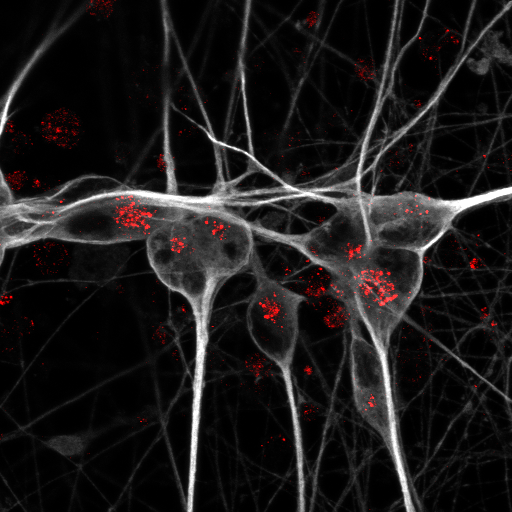

Abbildung: Menschliche Nervenzellen, die aus induzierten pluripotenten Stammzellen gewonnen wurden (grau): Um den ApoE-Rezeptor Sortilin nachzuweisen, haben die Forschenden ihn rot angefärbt. © Anna K. Greda, Aarhus University

Um zu verstehen, warum die ApoE4-Variante das Risiko für Alzheimer im Vergleich zu ApoE3 so dramatisch erhöht, haben die beiden Erstautorinnen der Studie, Dr. Anna Greda, Assistenzprofessorin in Willnows Arbeitsgruppe in Aarhus, und Dr. Jemila Gomes, die dort promoviert hat und nun als Postdoc in Willnows Berliner Team forscht, mit den Technologieplattformen „Pluripotent Stem Cells“ und „Electron Microscopy“ des Max Delbrück Center zusammengearbeitet. Die Forschenden verwendeten gentechnisch veränderte Mäuse, die das menschliche ApoE3- oder ApoE4-Gen trugen. In ihrem Mausmodell fanden sie heraus, dass das Protein ApoE3 mit einem Rezeptor namens Sortilin interagiert, um Fettsäuren in die Nervenzellen zu transportieren. ApoE4 hingegen stört die Funktion von Sortilin und verhindert so die Aufnahme der Lipide in die Neuronen.

Im nächsten Schritt prüften die Wissenschaftler*innen, ob ihre an Mäusen gewonnenen Erkenntnisse auch für die Gesundheit des menschlichen Gehirns relevant sind. Sie nutzten dafür Neuronen und Astrozyten mit verschiedenen ApoE-Genvarianten, die sie aus menschlichen Stammzellen gezüchtet hatten. In den gezüchteten Zellen konnte das Team erneut beobachten, dass ApoE3 es den Neuronen ermöglichte, langkettige Fettsäuren zu verstoffwechseln – während ApoE4 diese Fähigkeit unterband.